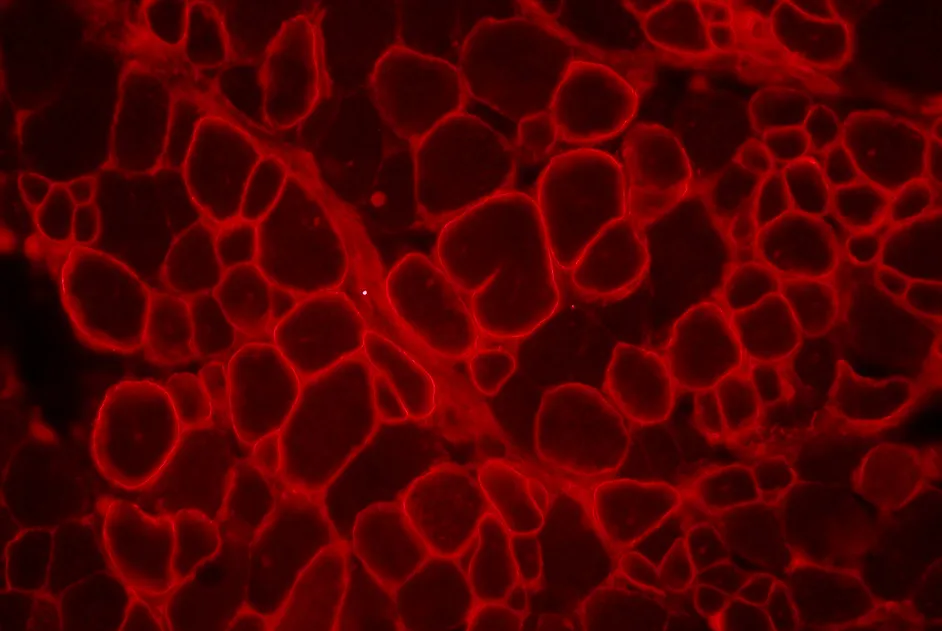

Maladie de Brody : MG53 réduit l’activité de SERCA1

Mise en évidence d’une interaction de la mitsugumine 53 avec la pompe à calcium, SERCA1, qui diminuerait l’activité de SERCA1.